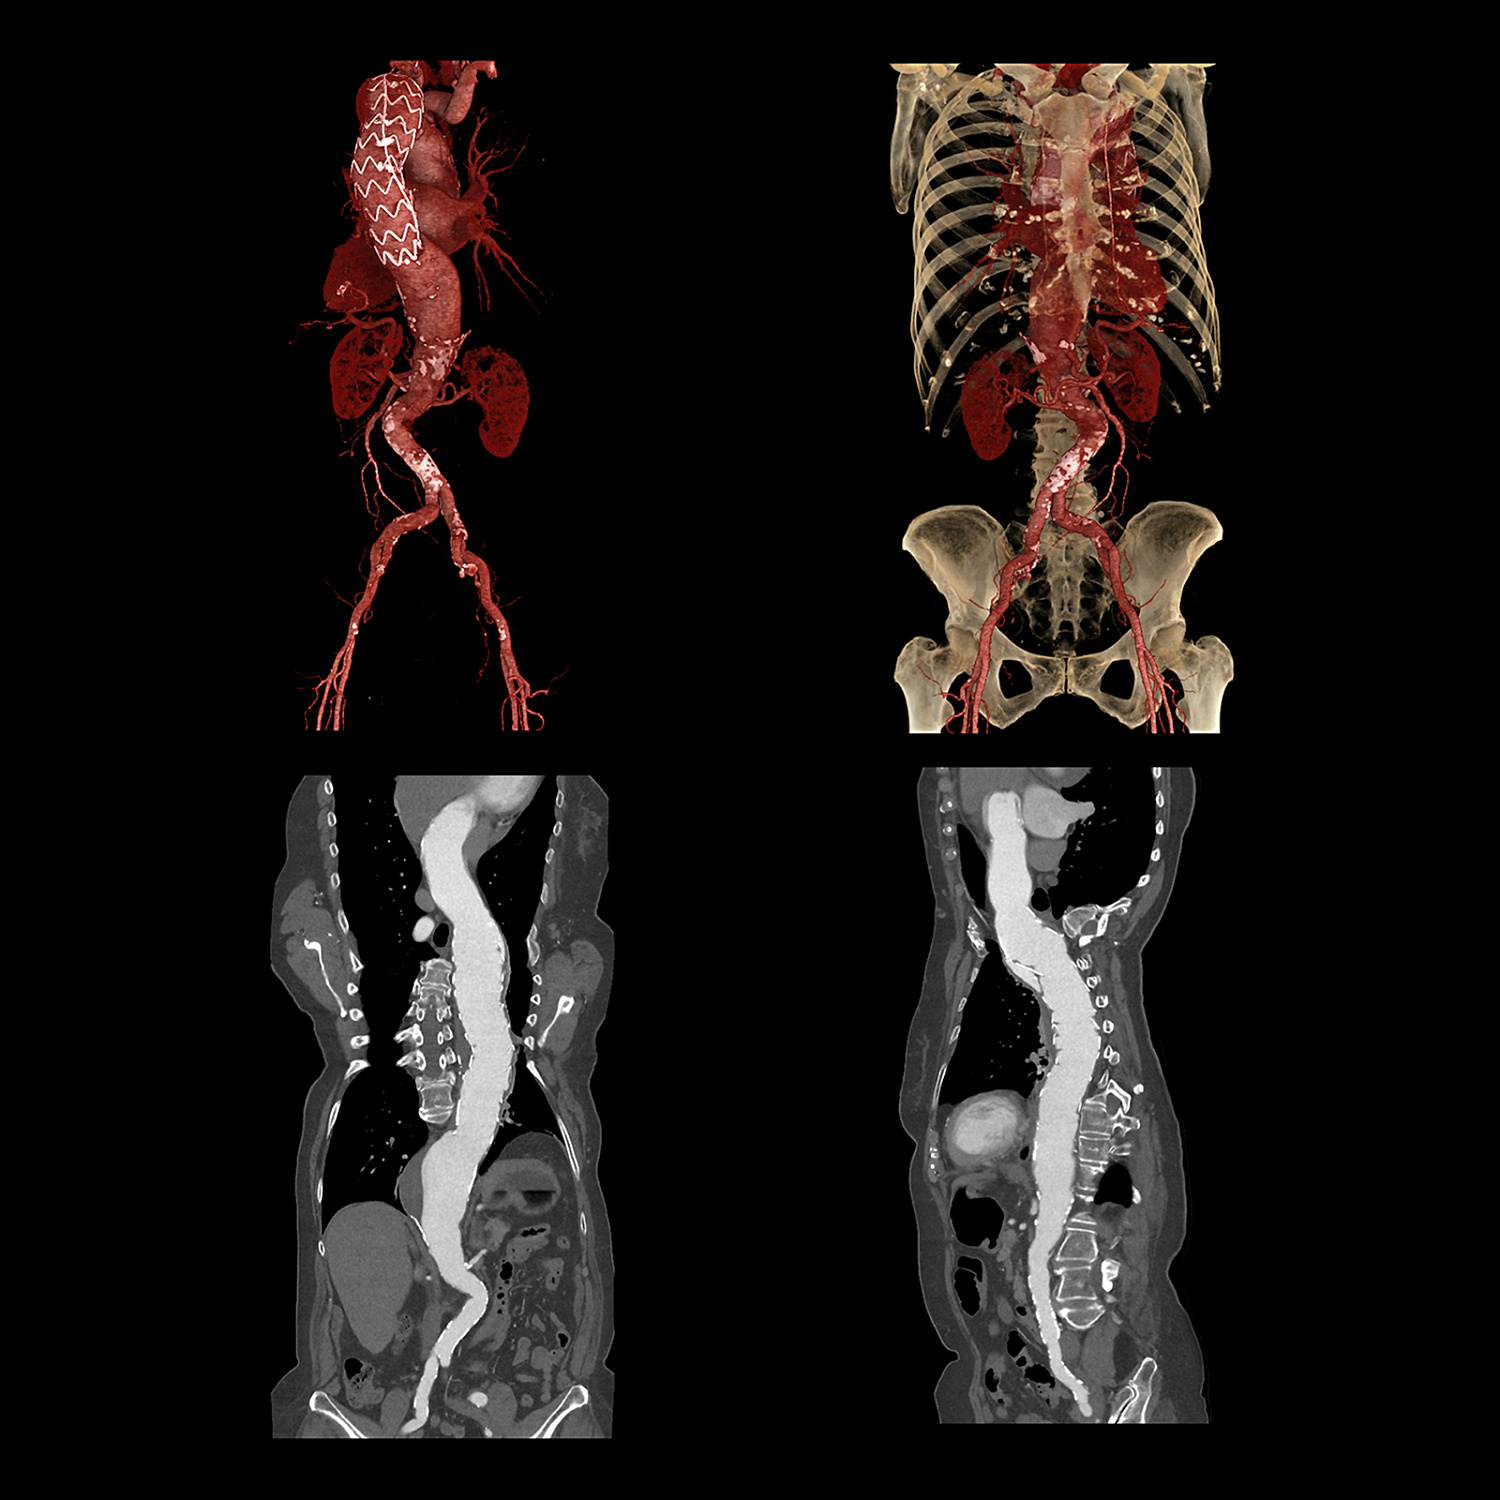

Спектральная визуализация с глубоким обучением

Система Deep Learning Spectral CT от Canon Medical была разработана, чтобы вывести ваши возможности визуализации на совершенно новый уровень.

Aquilion ONE (PRISM Edition) использует временные преимущества быстрого переключения кВ с модуляцией мА для конкретного пациента и сочетает их с реконструкцией глубокого обучения, которая обеспечивает превосходное разделение энергии и низкий уровень шума.